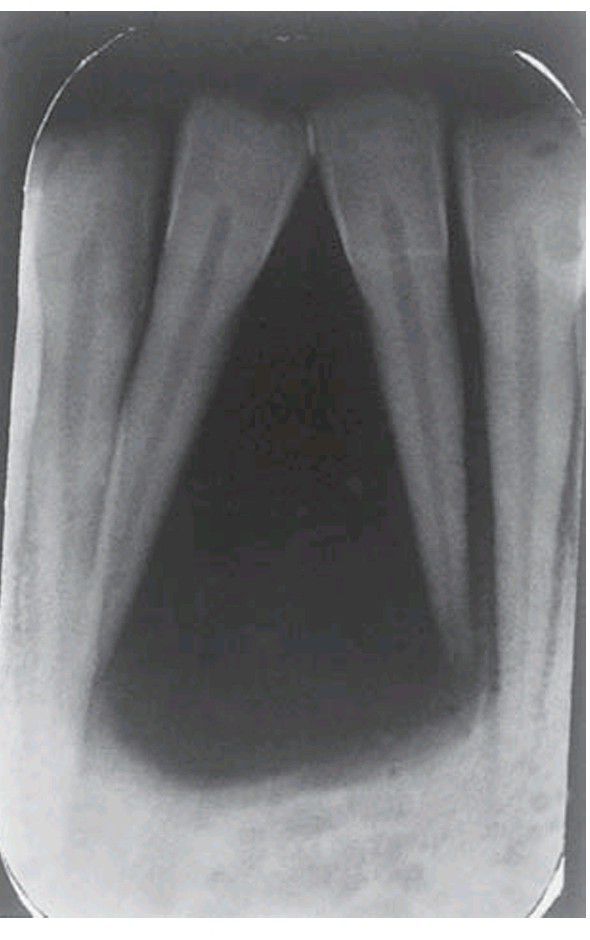

Hyperparathyroidism

. In this patient with hyperparathyroidism as a result of rejection of a kidney graft, there is a well-defi ned area of bone loss.